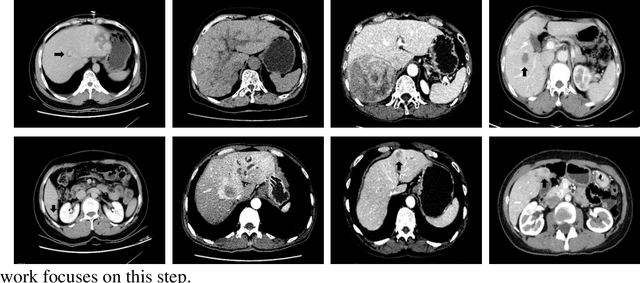

Abstract:Hepatocellular carcinoma (HCC) is the second most frequent cause of malignancy-related death and is one of the diseases with the highest incidence in the world. Because the liver is the only organ in the human body that is supplied by two major vessels: the hepatic artery and the portal vein, various types of malignant tumors can spread from other organs to the liver. And due to the liver masses' heterogeneous and diffusive shape, the tumor lesions are very difficult to be recognized, thus automatic lesion detection is necessary for the doctors with huge workloads. To assist doctors, this work uses the existing large-scale annotation medical image data to delve deep into liver lesion detection from multiple directions. To solve technical difficulties, such as the image-recognition task, traditional deep learning with convolution neural networks (CNNs) has been widely applied in recent years. However, this kind of neural network, such as Faster Regions with CNN features (R-CNN), cannot leverage the spatial information because it is applied in natural images (2D) rather than medical images (3D), such as computed tomography (CT) images. To address this issue, we propose a novel algorithm that is appropriate for liver CT imaging. Furthermore, according to radiologists' experience in clinical diagnosis and the characteristics of CT images of liver cancer, a liver cancer-detection framework with CNN, including image processing, feature extraction, region proposal, image registration, and classification recognition, was proposed to facilitate the effective detection of liver lesions.